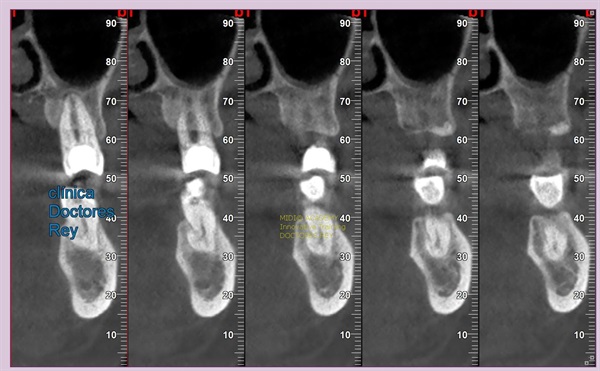

1- Implante de 9 mm de diámetro en maxilar superior post extracción + PRF. MIDI® TECHNIQUE®, no drill.

IMPLANTE EN MAXILAR SUPERIOR post extracción de diametro amplio 9 mm.

1- Implante de 9 mm de diámetro en maxilar superior post extracción + PRF. MIDI ®TECHNIQUE®, no drill.